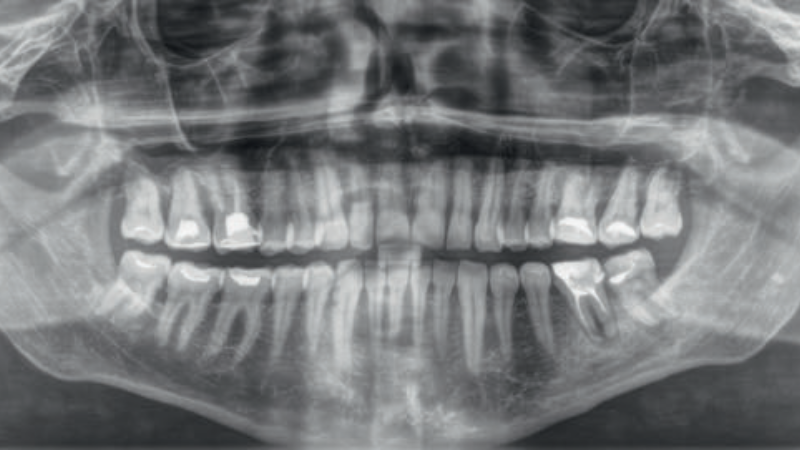

- Opis przypadku: utrata części wypełnienia korony zęba 36 oraz rozrzedzenie struktury tkanki kostnej okołowierzchołkowej w badaniu OPG.

- Opis ponownego leczenia kanałowego dolnego trzonowca.